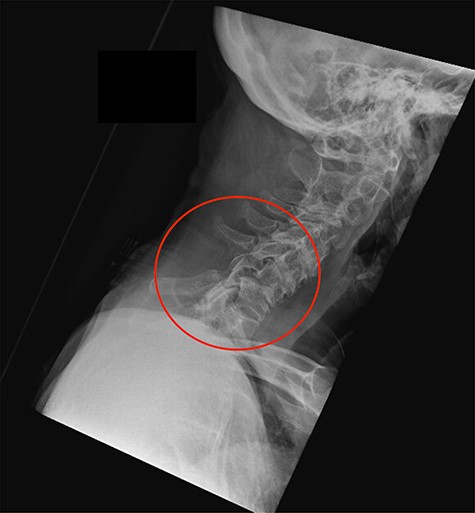

Two weeks later the patient was reviewed at home by her general practitioner due to ongoing neck pain, left shoulder pain and subjective numbness and weakness in her left arm. Upon assessment, it was noted that she held her neck in a flexed position and was unable to straighten the neck. The general practitioner arranged for an urgent review by the orthopaedic team in the nearest hospital. On assessment they recognized the potential for a significant injury and arranged an x-ray and a MRI of the cervical spine. Fig. 3 shows the lateral cervical spine radiograph demonstrating an anterior subluxation of the C6 vertebrae on C7 and significant malalignment between the spinous processes of C6 and C7.

Lateral cervical spine radiograph at the time of representation with the level of injury indicated.